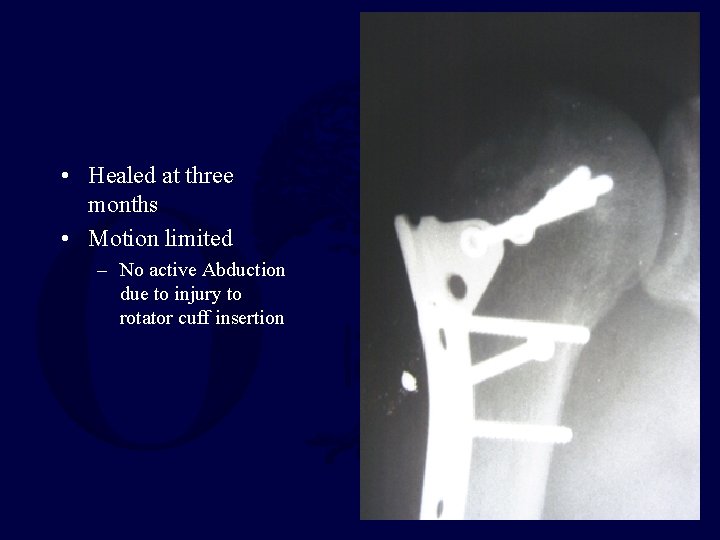

• Healed at three months • Motion limited – No active Abduction due to injury to rotator cuff insertion